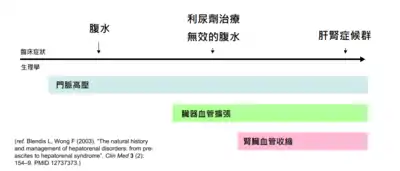

研究认为,肝衰竭會改变肠道的血液循环、肾血流量和肾的血管紧张度。因此,肝肾综合征患者的肾衰竭主要是導因於血流动力学的变化,而非肾组织的直接破坏。肝肾综合征患者的肾脏无论在巨觀上或微觀下的病理型態都是正常的,甚至若将之置于健康的环境中(如把他们移植给一个有着正常肝脏的患者),它們仍可正常发挥功能。临床上,肝肾综合征的诊断需對疑似肝肾综合征的患者進行实验室生化指标检查。肝肾综合征可分為兩種類型:1型以快速的肾功能减退为主要表现;2型则表现为腹水的产生,且無法以常规剂量的利尿剂控制。

肝肾综合征是一种常并发于肝硬化及爆发性肝衰竭(较少见)的肾功能衰竭[1]。病理生理学改变主要为肾血管收缩及肠循环血管舒张[2]。基于2种不同机制的肾衰竭,HRS可分为1型和2型,兩者均可发生于肝硬化和猛爆性肝衰竭的患者;也均可見到腎功能惡化導致的血清肌酸酐上升及肾脏肌酸酐清除率下降[3]。

兩種類型的肝肾综合征均由肝功能下降、循环失常和肾衰竭引起。这三个病理生理学改变在进行到终末期之前可能不会表现出明显的症状,因此,肝肾综合征的诊断需依賴实验室检查指标的变化。多数肝肾综合征的患者有肝硬化,因此可能出現與肝硬化相同的症状,如黄疸、肝性腦病變、营养不良和腹水[2]。利尿剂治疗无效的腹水是2型肝肾综合征的重要特征。腎衰竭时可能出现少尿,但仍有些肝肾综合征患者有正常的尿量。这些症状和表徵在肝肾综合征的病程中都不一定会出现,因此無法作為肝肾综合征的诊断标准或依据。肝肾综合征的诊断需對可能出现肝肾综合征的病例進行实验室检查,并排除其他可能引起这些指标改变的疾病[3]。

肾血流低灌注理论中包含了肾素-血管紧张素系统的激活,而醛固酮可以与肾脏远曲小管上的盐皮质激素受体结合,造成钠的重吸收增加[8][12],这是肝硬化腹水的发病机制中的关键过程。有假說認為腹水和肝腎症候群同屬一個疾病光譜,皆由臟器血管擴張所致[8]。